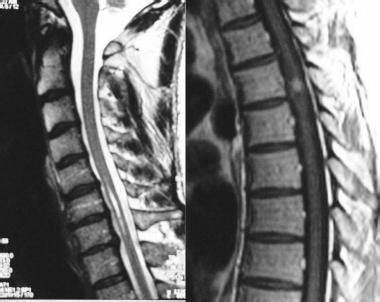

脊髓肿瘤,是在脊柱内发现的组织的异常生长。它们可以是良性的(非恶性的),也可以是恶性的(恶性的)。起源于脊柱的肿瘤称为原发性肿瘤。无论是癌性的还是非癌性的,脊柱内的肿瘤在生长过程中会导致严重的健康问题,并对脊髓造成压力。通常需要立即治疗。

立即治疗脊髓肿瘤是取得成功的关键。大多数的脊髓肿瘤是通过手术治疗的。如上所述,即使是非癌性肿瘤也会继续生长,压迫脊髓并阻塞滋养脊髓细胞的血管。这可能严重影响儿童的功能能力,甚至可能导致完全和长期性瘫痪。

手术的目的是切除或缩小肿瘤的大小,减轻肿瘤对脊柱的压迫。一旦手术完成,病理学家检查肿瘤组织以确定肿瘤的确切类型。这被称为肿瘤分类,它是基于肿瘤来源的细胞类型。在对肿瘤进行分类后,医生会给它一个数字来表示它生长的速度。这叫做肿瘤分级。快速生长的肿瘤给予较高的级别,而侵袭性较弱的肿瘤给予较低的级别。

在德国,1992年,INC国际神经外科医生集团旗下组织国际神经外科顾问团(WANG)成员,巴特朗菲教授提出了半椎板切除术、用于治疗脊柱髓内病变的一种技术方法。半椎板切除术属于微创治疗,伴随术中超声检查,术中神经生理学监测和细致的显微外科技术,较大切除肿瘤的同时尽可能避免损伤脊柱功能和结构,术后疼痛较轻,患者可尽早进行康复训练,住院时间较短,术后脊柱不稳定性较椎板切除术减少。